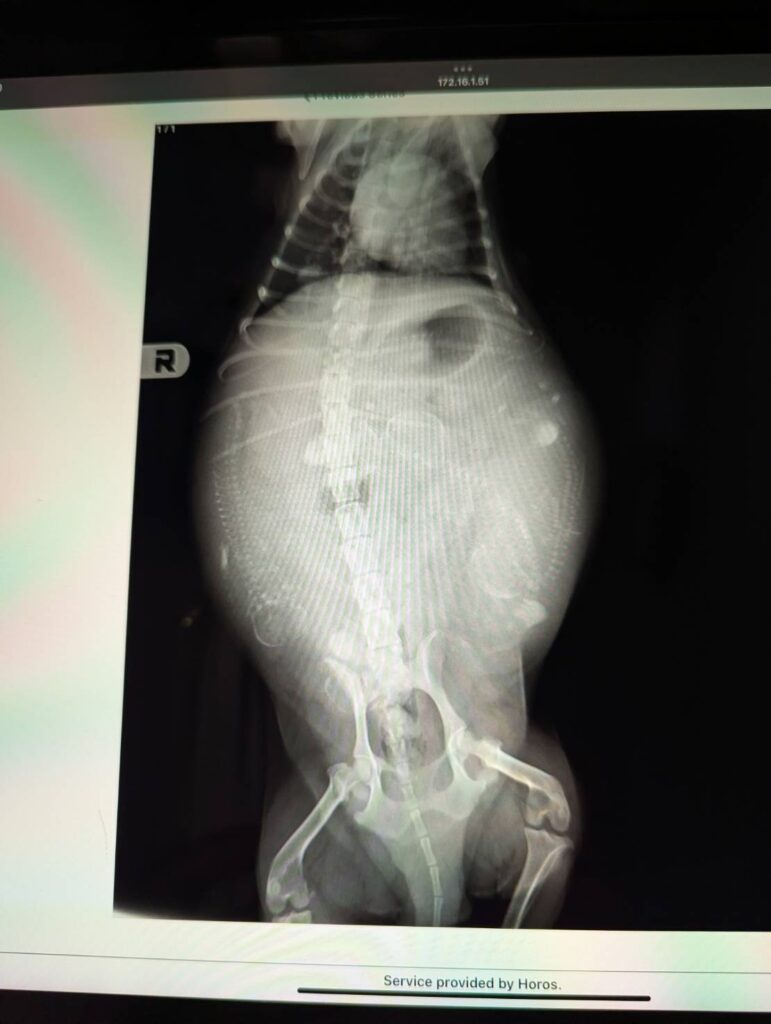

カメリア レントゲン検査

リアが妊娠して55日過ぎ。

動物病院へ子犬の数を確認しに、レントゲン撮影に行ってきました。

今回はゆっくりおなかが大きくなった気がしたので、前回の6頭、7頭のようにあまり子犬の数も多くないかもと話していましたが、レントゲンで確認したところ5頭は居そうです。